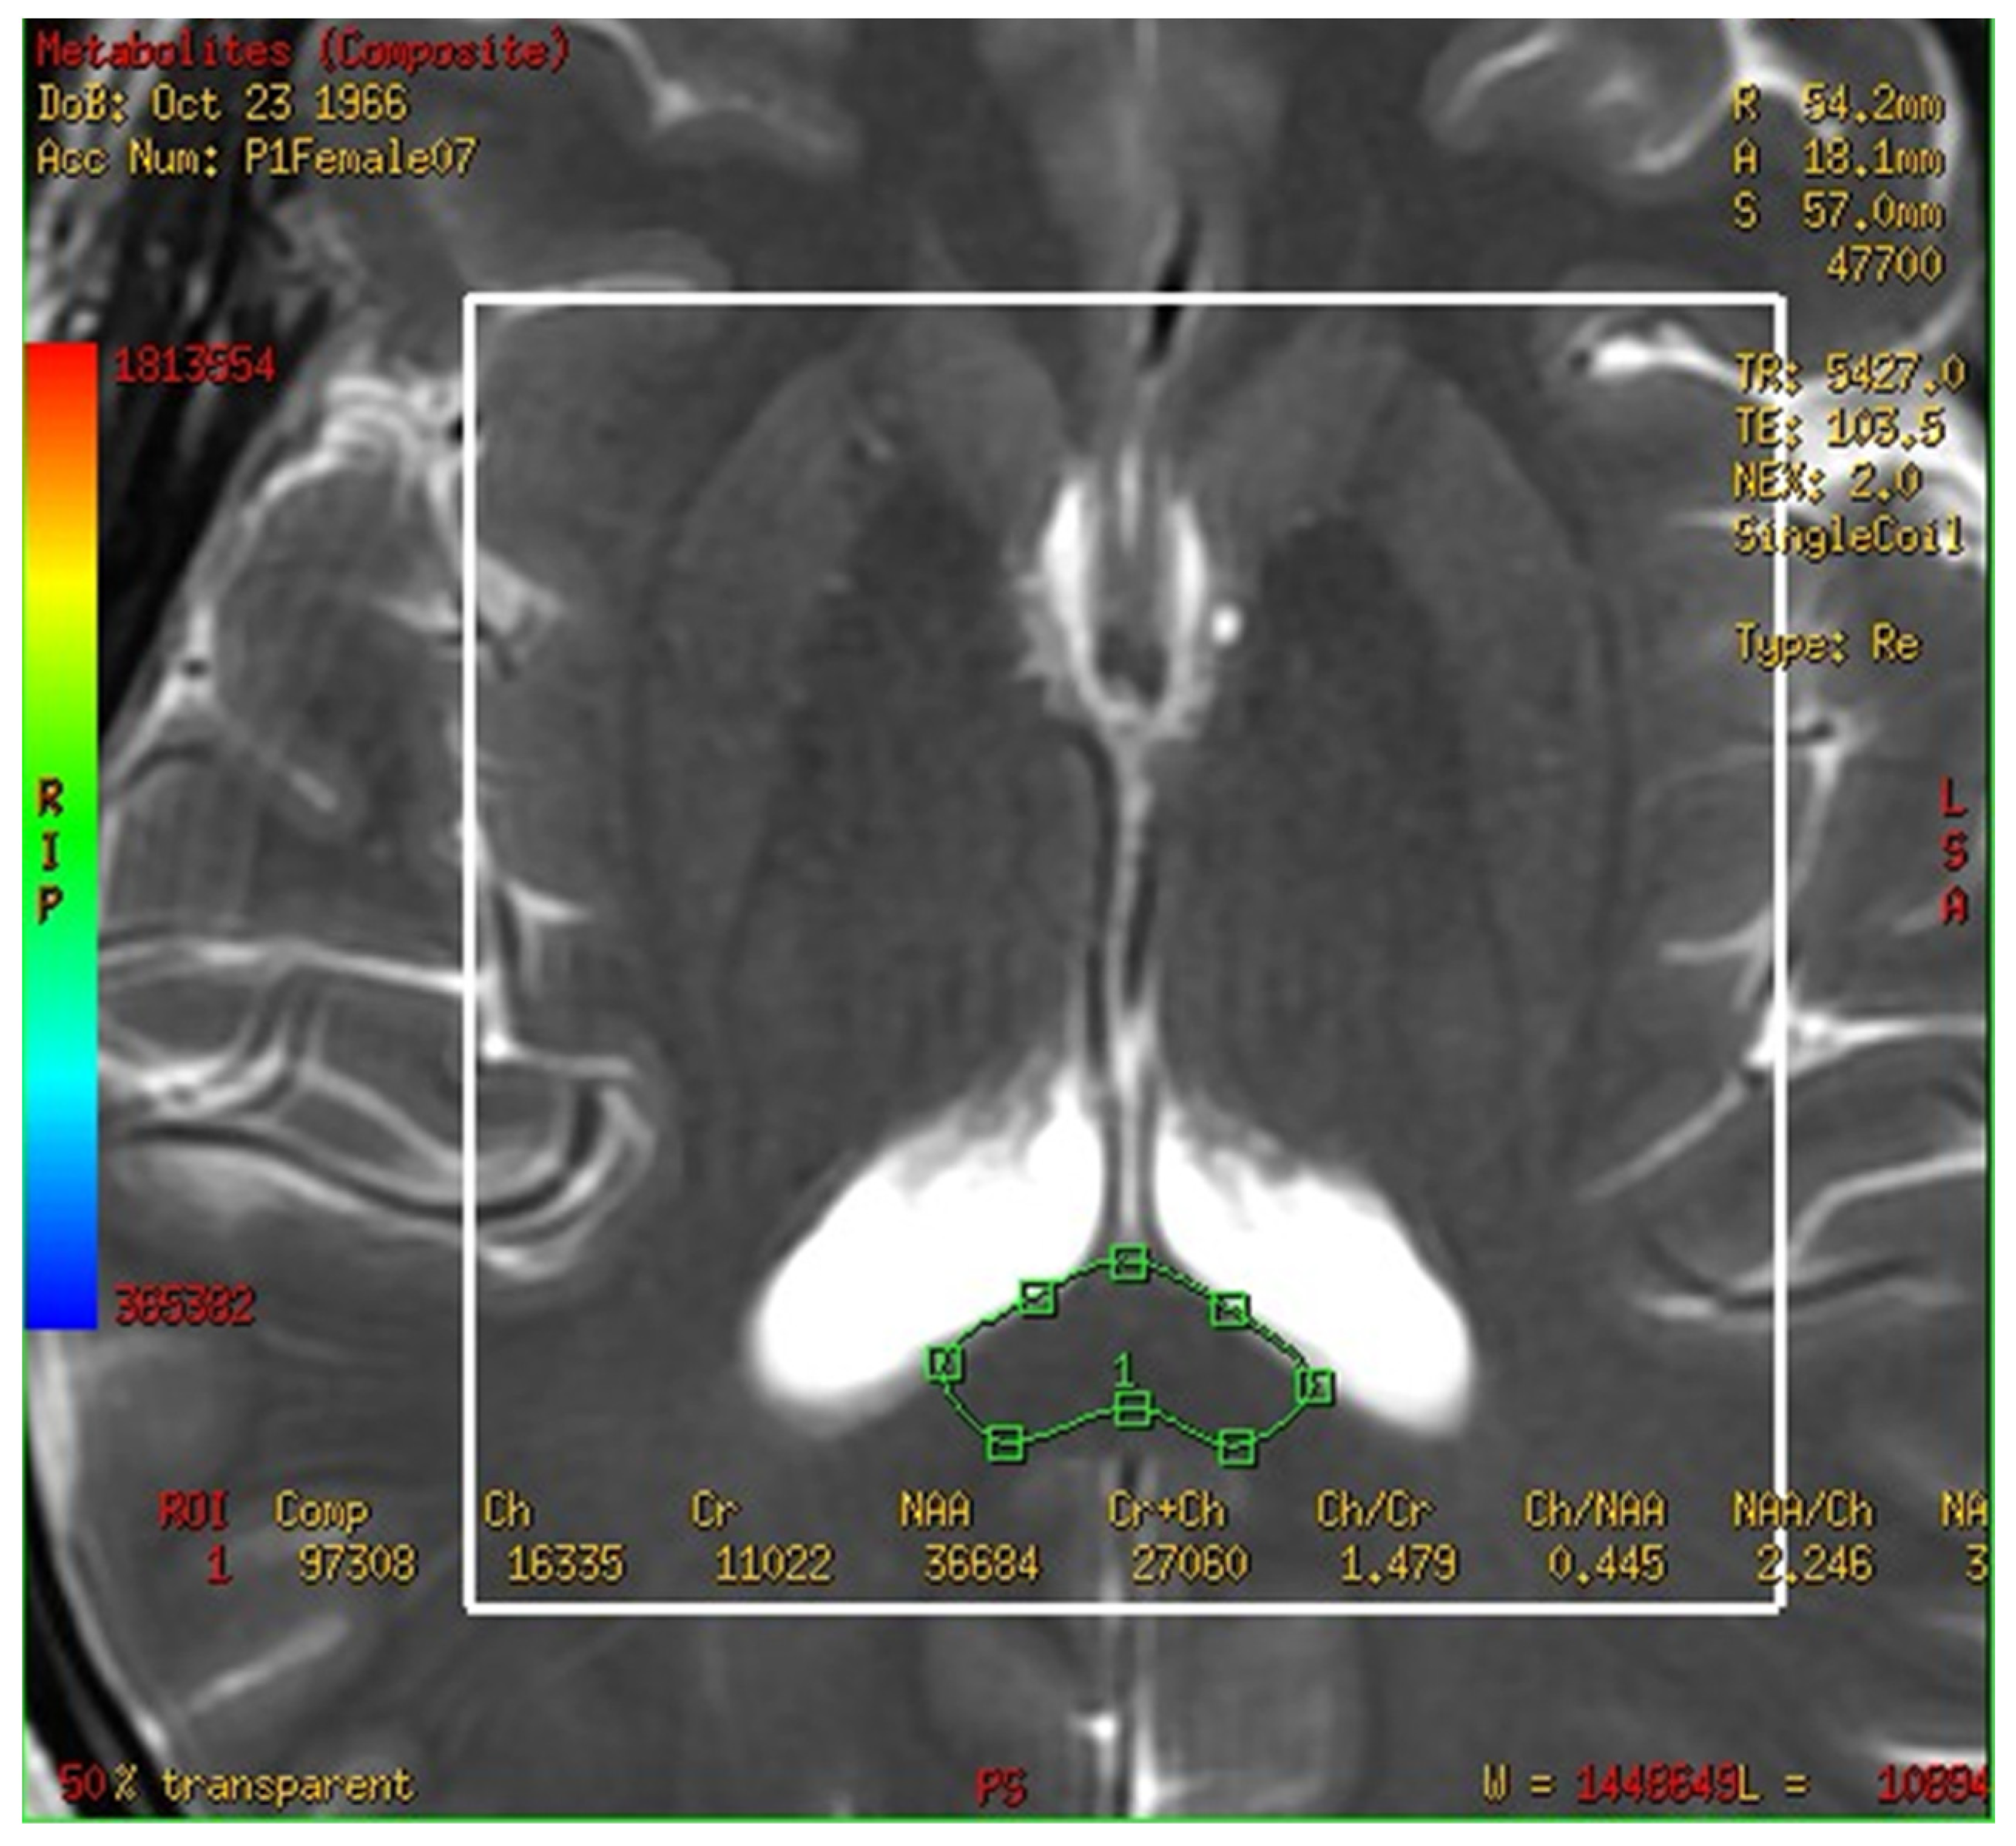

In this study, a medical 1.5 T MRI machine (GE Signa HDxt Medical Systems, Waukesha, WI, USA) and a standard head coil (Head Coil) in Camillians Saint Mary’s Hospital Luodong were used to receive signals from brain images of MRI T1 and T2 sequences, and 1H-MRS with 3D-CSI (echo time (TE) 144 ms, repetition time (TR) 1000 ms) for all participants. The range of chemical shift was set from 0 to 4 ppm, as this could include the signal of most metabolites in the brain, and the volume of each voxel was set at approximately 1–1.5 square centimeters. The measurements were performed as follows: First, brain images of T1 and T2 sequence with 3-Plane localization (sagittal, axial, and coronal planes) were obtained to locate the hippocampus and corpus callosum in the brain. Second, the three-dimensional space of the hippocampus and corpus callosum was manually marked and chosen on the image by a technician. Subsequently, the three-dimensional space of the hippocampus was divided into the total (bilateral), right, and left hippocampi. Third, the MRS with 3D-CSI was performed in the chosen location of the hippocampus (Figure 1) and corpus callosum (Figure 2). The signal intensities of choline (Cho), N-acetyl aspartate (NAA), creatine (Cr), and myo-inositol (MI) in the total (bilateral), right, and left hippocampi and the corpus callosum were measured and recorded in arbitrary units and used for statistical analysis.

On comparing the metabolites in the corpus callosum between the MCI and control group, the ratio of normal Cr between two groups compared as follows: NAA/Cr (0.778 ± 0.333 vs. 2.506 ± 1.648, p = 0.020), MI/Cr (0.062 ± 0.056 vs. 0.222 ± 0.136), and the level of signal intensities of Cr (4200 ± 2100 vs. 16,200 ± 11,800, p = 0.02) were significantly lower in the MCI group (Table 3). The result was easily visible in the color map of the MRS with 3D-CSI. For example, the MRS with 3D-CSI color map of NAA showed a red color (high signal) in the corpus callosum area of the control group, while it showed a blue color (low signal) in the corpus callosum area of the MCI group (Figure 4). For the levels of signal intensities of Cho/Cr, there was a trend of lower intensity at the corpus callosum in the MCI group compared with the control group, but without significant difference.

Figure 2. Magnetic resonance spectroscopy with three-dimensional chemical shift images in the chosen location of the bilateral corpus callosum (green markup). The signal intensities of metabolites were measured and recorded.

Figure 4. Magnetic resonance spectroscopy with three-dimensional chemical shift images color map of N-acetyl aspartate. The left figure shows red color (high signal intensity) in the corpus callosum area (green markup) of control group. The right figure shows blue color (low signal intensity) in the corpus callosum area (green markup) of mild cognitive impairment group.